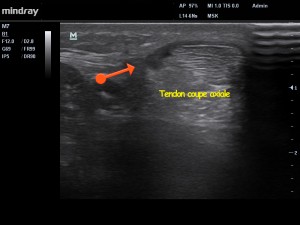

Fig1. La flèche rouge indique la présence de la paratendinopathie.

Chez notre patient, l’échographie (Fig 1 – 3 ) montre la présence d’un mécanisme inflammatoire actif, avec présence d’un exsudat au niveau de para-tendon.  On parle précisément d’inflammation fibrineuse dans notre cas. SI la pathologie s’installe dans le temps, la présence de fibrinogène (grosse protéine présente dans le plasma sanguin) va conduire à la prolifération de fibroblastes (petites cellules notamment impliquées dans la fabrication du collagène et certaines protéines du tissu conjonctif ). Le para-tendon va alors s’épaissir, et des adhérences vont se former entre le para-tendon et le tendon, mettant en péril la vascularisation de ce dernier.